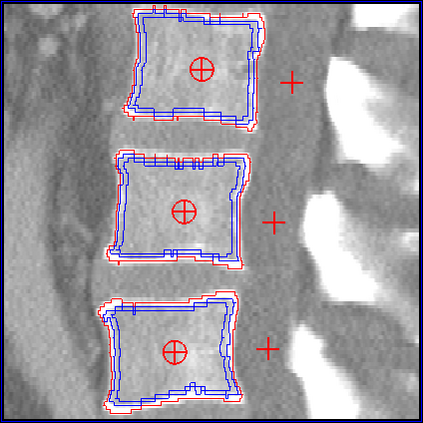

In this paper we present a new 3D segmentation approach for the vertebrae of the lower thoracic and the lumbar spine in spiral computed tomography datasets. We implemented a multi-step procedure. Its main components are deformable models, volume growing, and morphological operations. The performance analysis that included an evaluation of accuracy using the European Spine Phantom, and of intra-operator precision using clinical CT datasets from 10 patients highlight the potential for clinical use. The intra-operator precision of the segmentation procedure was better than 1% for Bone Mineral Density (BMD) and better than 1.8% for volume. The long-term goal of this work is to enable better fracture prediction and improved patient monitoring in the field of osteoporosis. A true 3D segmentation also enables an accurate measurement of geometrical parameters that can augment the classical measurement of BMD.